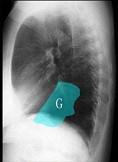

问题 如图所示正常胸部X线影像图像上,该英文字母所代表的肺段为 ( )

选项 A.内基底段 B.前基底段 C.外基底段 D.后基底段 E.背段

答案 B